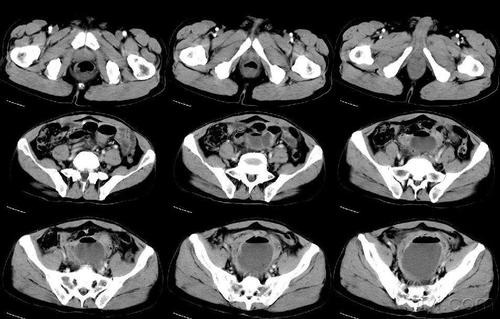

盆腔类的疾病在女性中是比较常有的,一些妇科炎症也没办法避免,如果不改善和治疗的话,对生活和身心都会造成很大的影响,严重的也会对生育造成影响,建议女性要按时做好妇科检查,及时发现并且治疗。那么,盆腔ct可以检查什么呢?

首先,只要是盆腔内的任何病变,都能检查出来,比如肠道肿瘤、阑尾发炎、泌尿系统疾病、宫颈疾病、附件肿瘤等等,作为女性要多预防这方面的疾病,定期去做妇科检查、盆腔检查是有必要的,能及时预防或者发现一些疾病,尽早进行治疗。